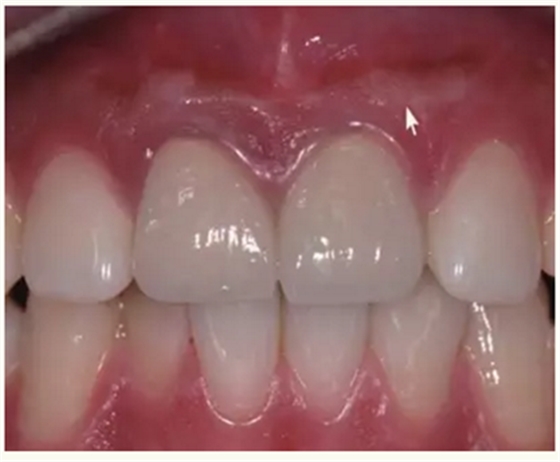

▲术后,手术切口处疤痕